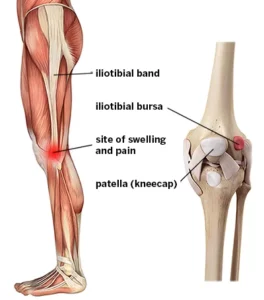

The iliotibial bands (ITB), a long, flat, and strong tendonous structure, originates from the gluteus maximus (TFL) and tensor facia lacta (TFL), muscles at the hip. It runs along the outside of your thigh. It is located in the outer region below the knee joint, and it is also known as GerdyaEUR ™’s tubercle at the lateral condyle.

Iliotibial Band Friction Syndrome (also called ITBS or Iliotibial Band Syndrome) is an inflammation and painful irritation that occurs at the area where the iliotibial bands crosses the lateral epicondyle. This is located just above the outside edge of the knee joint.